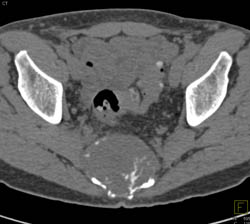

Chordoma